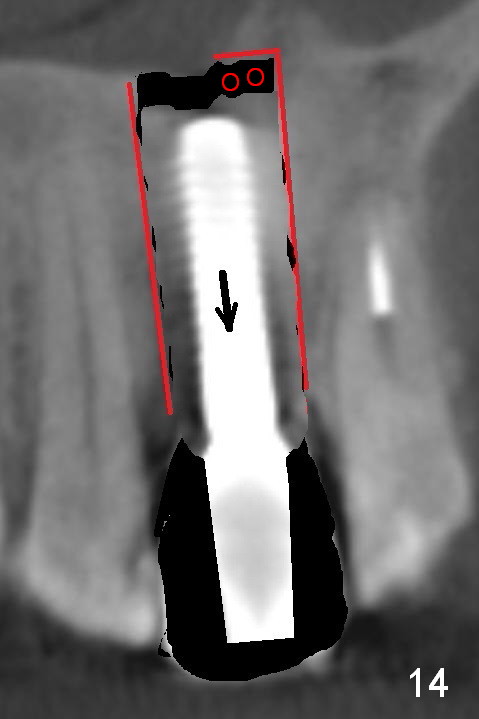

Fig.10 is a sagittal section of the implant (arrowheads: nasal floor). It is apparent that there is enough space (Fig.11,12 (PA)) for osteotomy (Fig.13 red lines: A: angled Titanium abutment). With the palatal mucoperiosteal flap attached the implant/bone segment, it is moved apically (Fig.14). Coronally the coronal portion is repositioned palatally while the apical portion buccally (Fig.15 arrows). Is the segment stable?